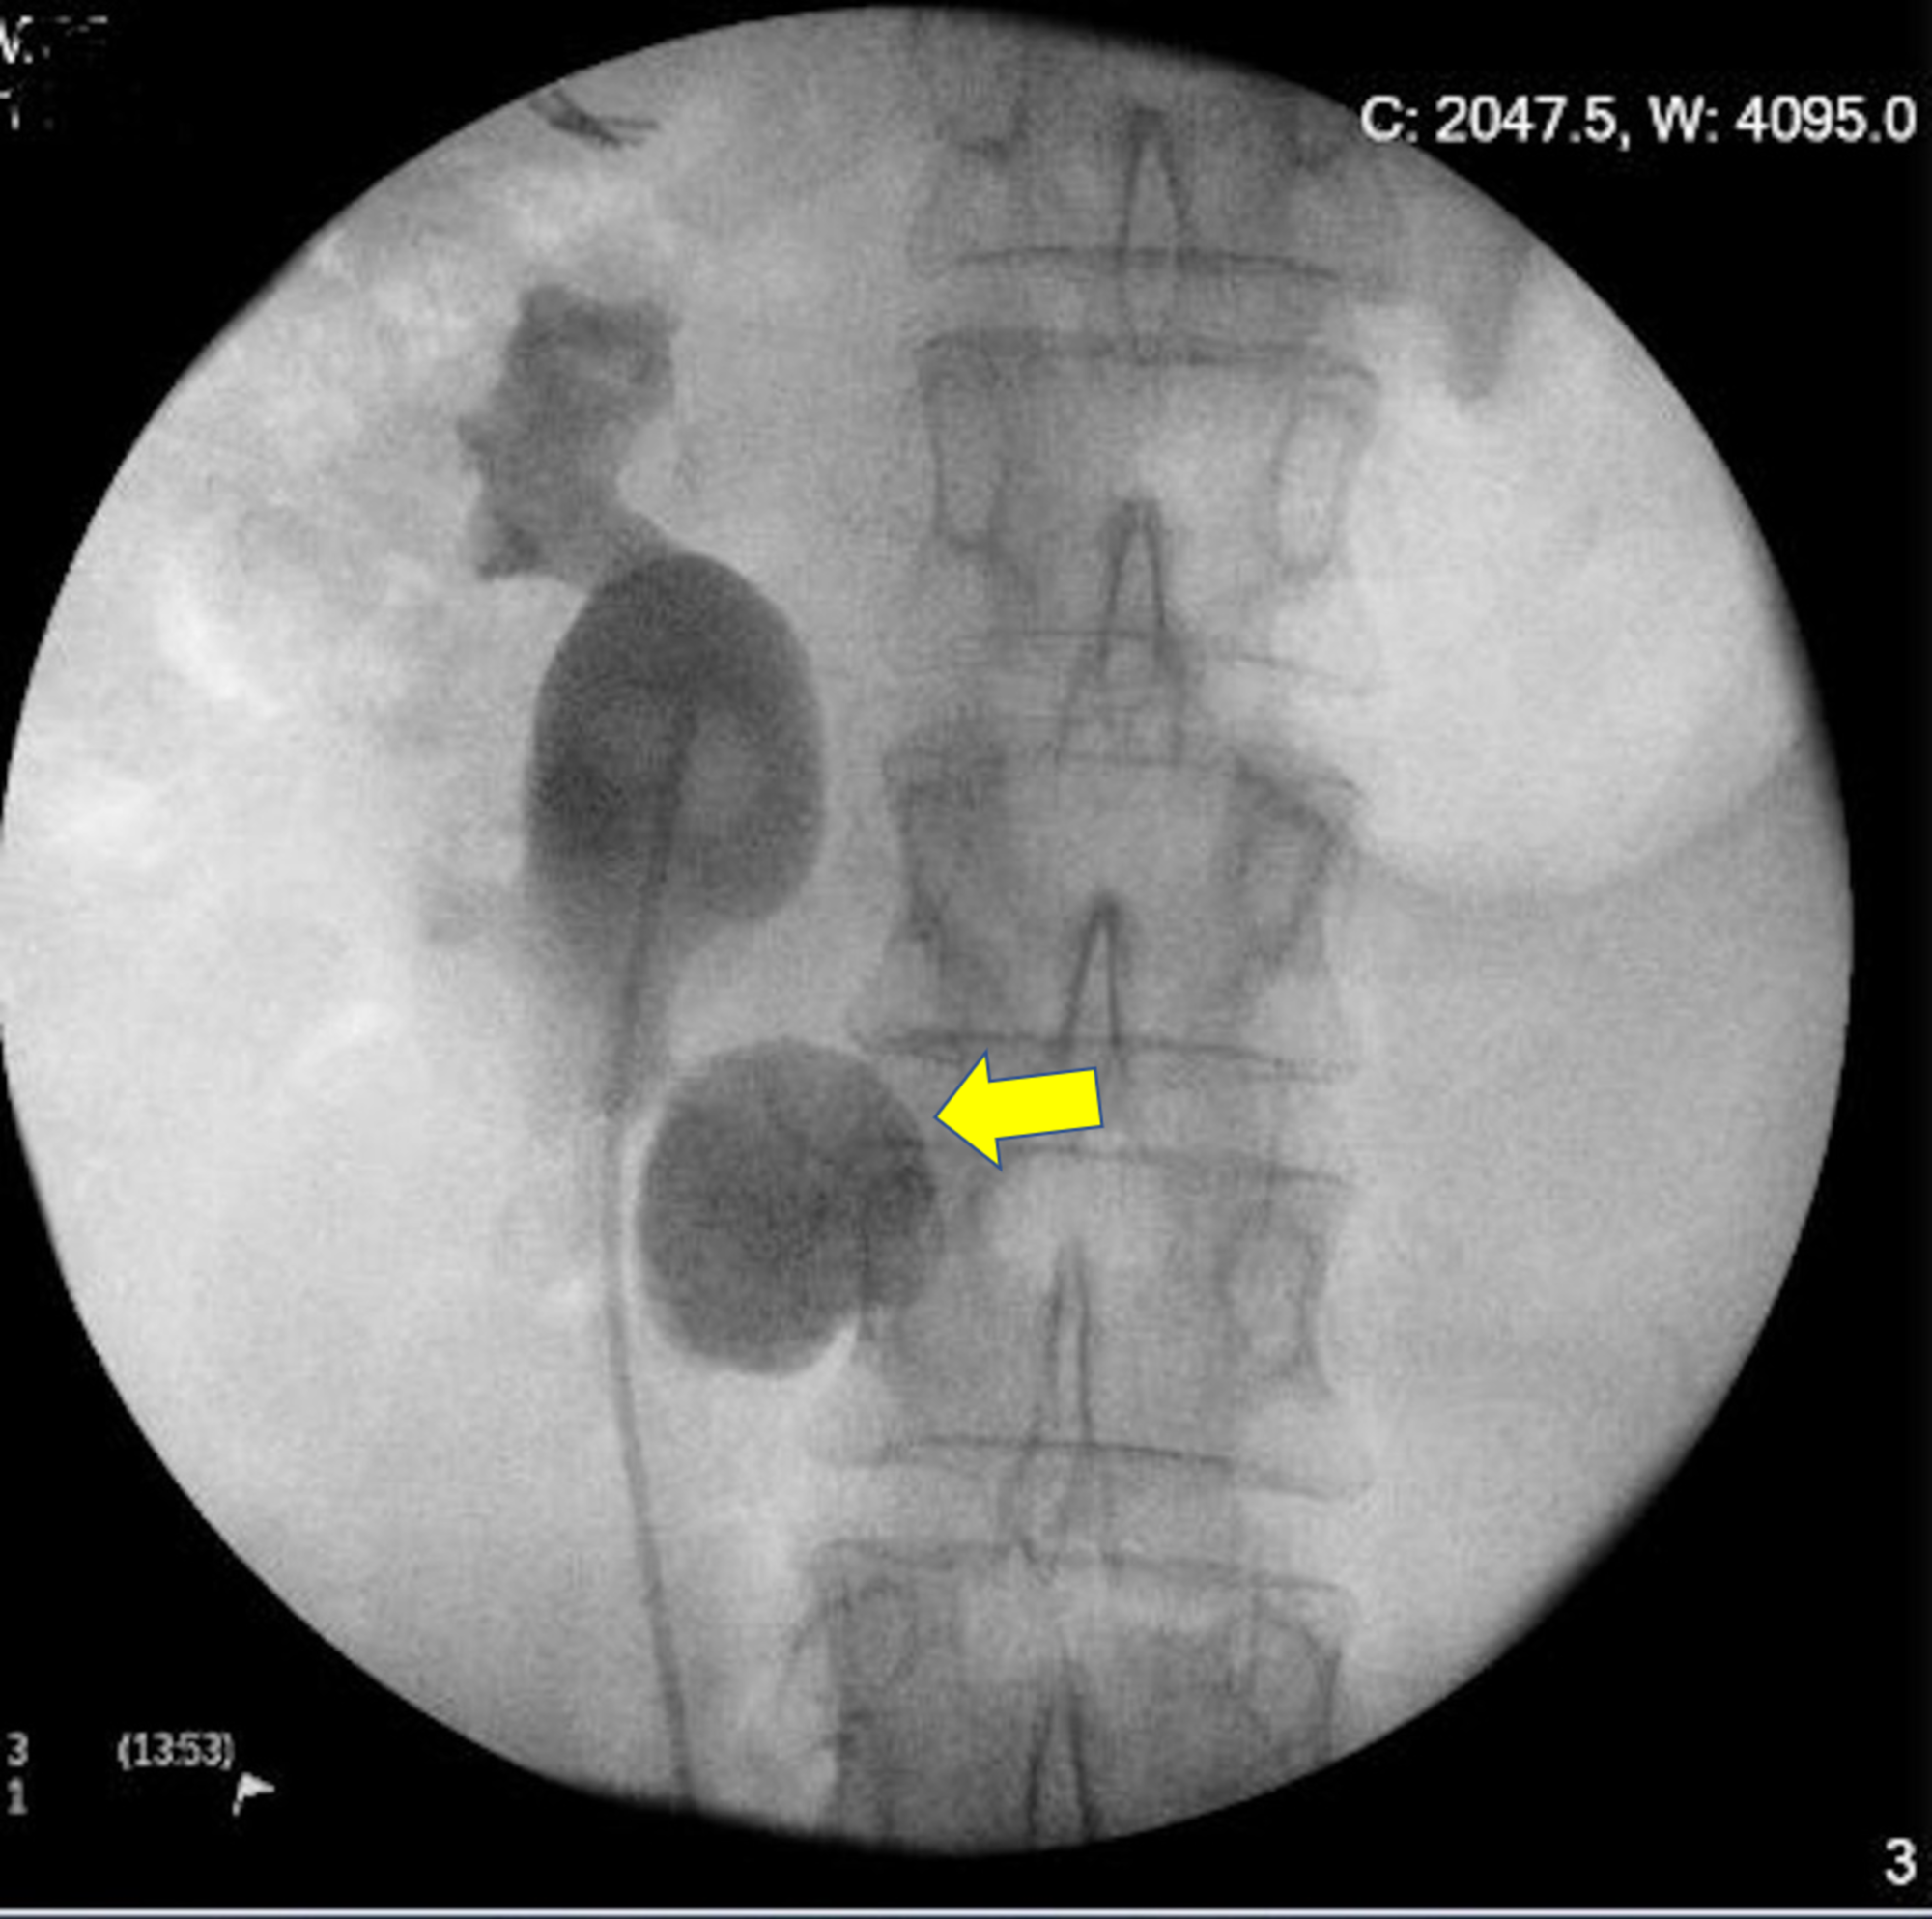

Horseshoe kidney on intravenous pyelogram Image

Horseshoe kidney on intravenous pyelogram Image Horseshoe Kidney Ivp It consists of two distinct functioning kidneys on each side of. Horseshoe kidneys are the most common fusion defect of the kidneys occurring in approximately 1:500 individuals. The horseshoe kidney (hsk) is the most common congenital fusion abnormality of the urinary tract, which combines three anatomic. Horseshoe kidneys is a congenital condition of the kidneys which produces a characteristic ivp. Horseshoe Kidney Ivp.